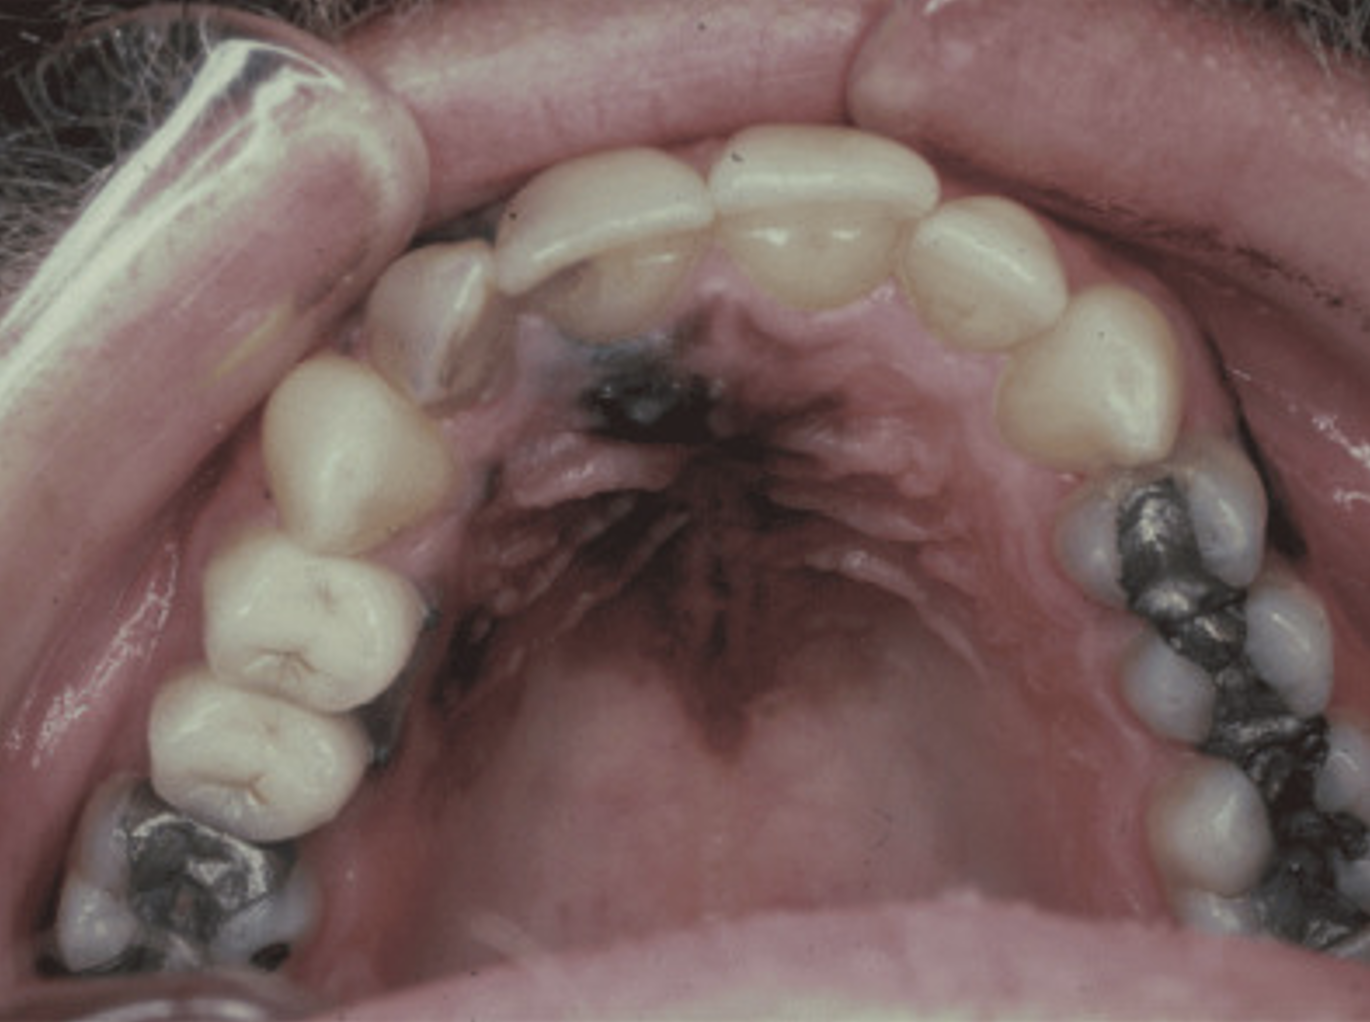

example of Mucosal Melanoma

Mucosal (oral, sinonasal, gastrointestinal tract, anal or vaginal) melanoma

These images were published in Pathology of Melanocytic Tumors, Busam, K. J., Scolyer, R. A., & Gerami, P. Figure 14.3(A), Figure 24.13, Figure 23.2, pgs. 170, 267, 275. Copyright Elsevier Health Sciences (2018).